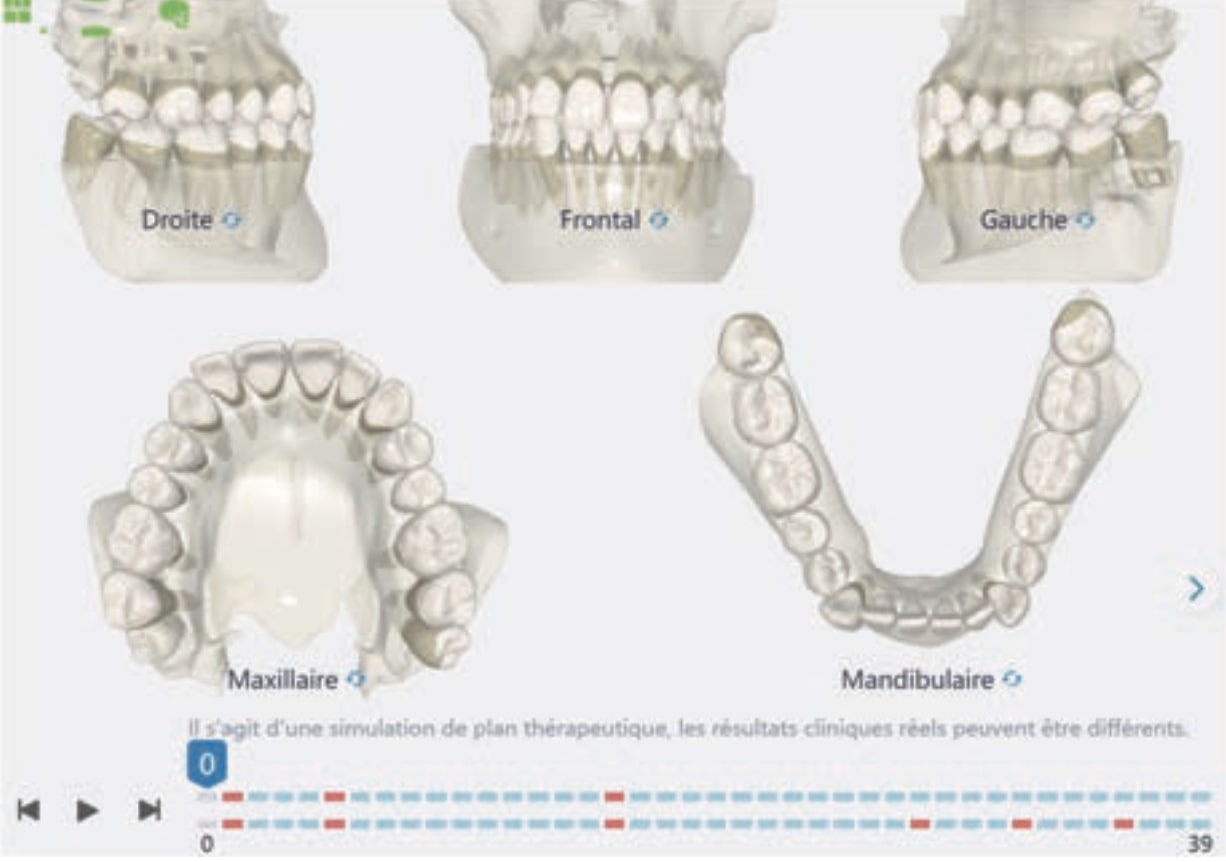

Treatment setup